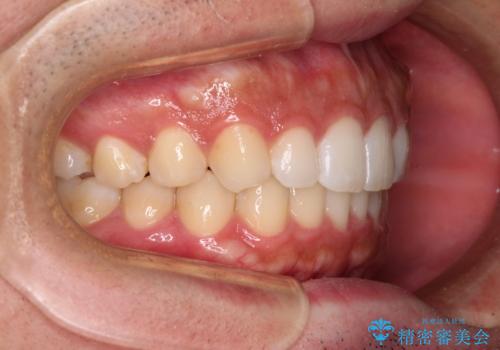

前歯のデコボコと突出感 インビザラインにて矯正治療

- 上下前歯のデコボコを気にして来院された患者様です。

インビザラインによる上下歯列の側方拡大と後方移動、IPR(歯と歯の間を削る)にるスペースの獲得により歯列を整えることとしました。

左上の小臼歯は捻転が強く、あえて180逆向きの状態で終了させる治療計画としました。

ご自宅と職場がともに遠方であったため、治療期間は長くなりましたが、患者様も我々も期待して以上に口元の突出感を改善することができました。